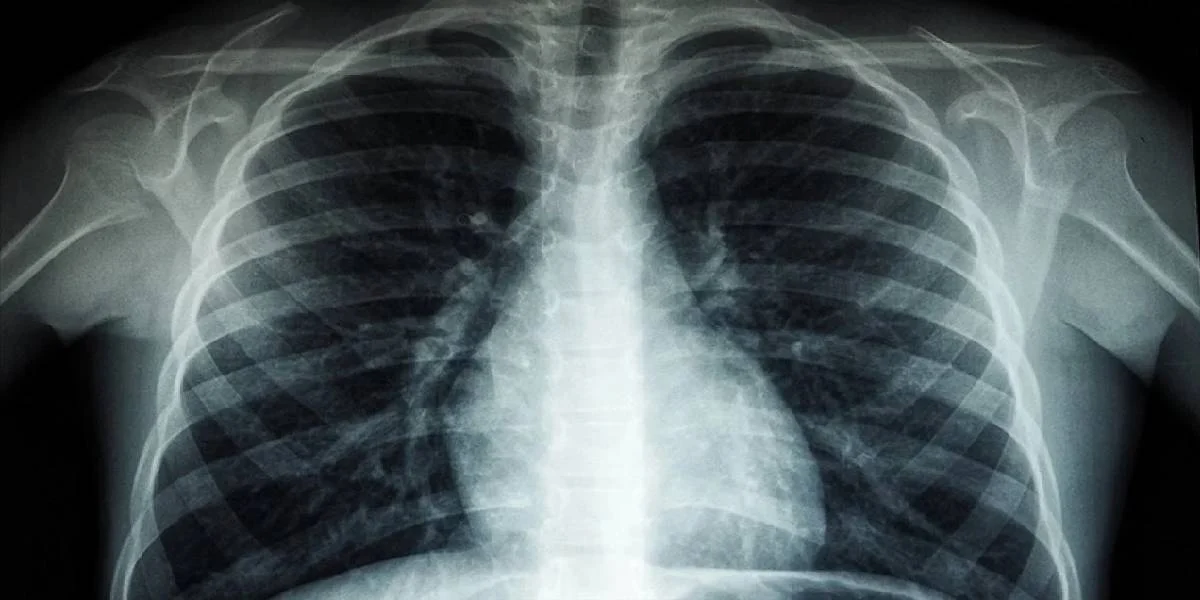

DSÖ Uyarıyor: Tüberküloz Vakalarında Rekor Artış Devam Ediyor!

DSÖ'nün raporu, tüberküloz vakalarında 2022'de kaydedilen yüksek rakamlara dikkat çekiyor, salgın sonrası tedavi hizmetlerinde iyileşme çağrısı yapıyor.

Dünya Sağlık Örgütü'nün (DSÖ) yayımladığı 2023 Küresel Tüberküloz Raporu'nda, 92 ülke ve bölgeye yer verildi. Söz konusu raporda, 2022 yılında 7,5 milyon kişiye tüberküloz tanısı konulduğu, bunun DSÖ'nün 1995 yılında tüberkülozu izlemeye başlamasından bu zamana kadar kaydedilen en yüksek rakam olduğu belirtildi.